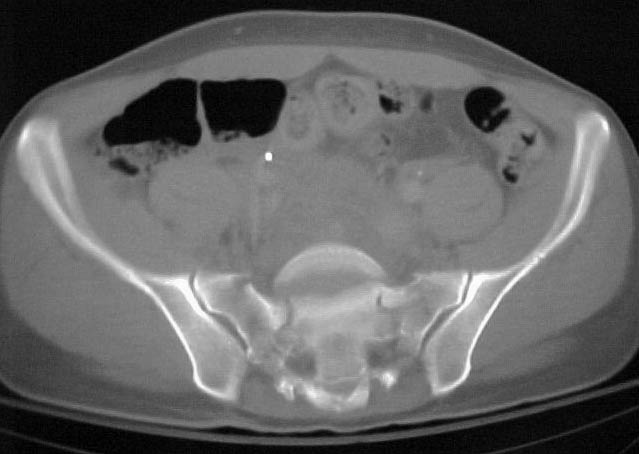

A 28 year old male jumped from the 4th floor on 11-25-2000 sustaining an L1 burst fracture that has been fixed anteriorly by the neurosurgeon with a strut between T12 and L2. A Kaneda device was placed anteriorly as well. My concern is the pelvic ring injury. There are bilateral sacral fractures through the foramen and a transverse element through the sacrum between S2 and S3. the lower part of the sacrum is displaced forward. Anteriorly there are right superior and inferior pubic rami fractures.

CT1